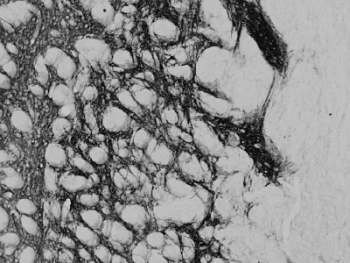

IHC staining of a PFA-perfused cryosection of mouse stria terminalis with PENK antibody at 0.02ug/ml. HRP-staining with Ni-DAB after Biotin-SP secondary.